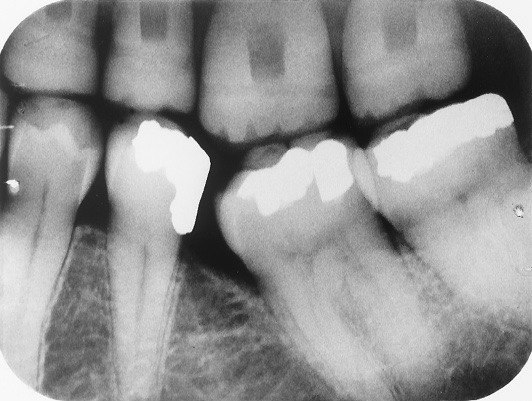

11. What is the radiolucency on the teeth # 1.1, 1.2, 1.3?

12. What is the condition showed by the arrow?

14. What condition can be seen on the root surface of tooth # 1.1.?